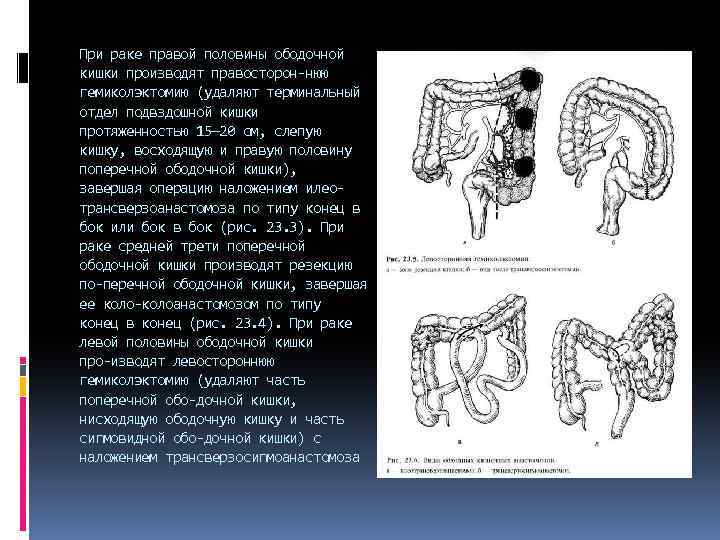

При раке правой половины ободочной кишки производят правосторон нюю гемиколэктомию (удаляют терминальный отдел подвздошной кишки протяженностью 15— 20 см, слепую кишку, восходящую и правую половину поперечной ободочной кишки), завершая операцию наложением илео трансверзоанастомоза по типу конец в бок или бок в бок (рис. 23. 3). При раке средней трети поперечной ободочной кишки производят резекцию по перечной ободочной кишки, завершая ее колоанастомозом по типу конец в конец (рис. 23. 4). При раке левой половины ободочной кишки про изводят левостороннюю гемиколэктомию (удаляют часть поперечной обо дочной кишки, нисходящую ободочную кишку и часть сигмовидной обо дочной кишки) с наложением трансверзосигмоанастомоза